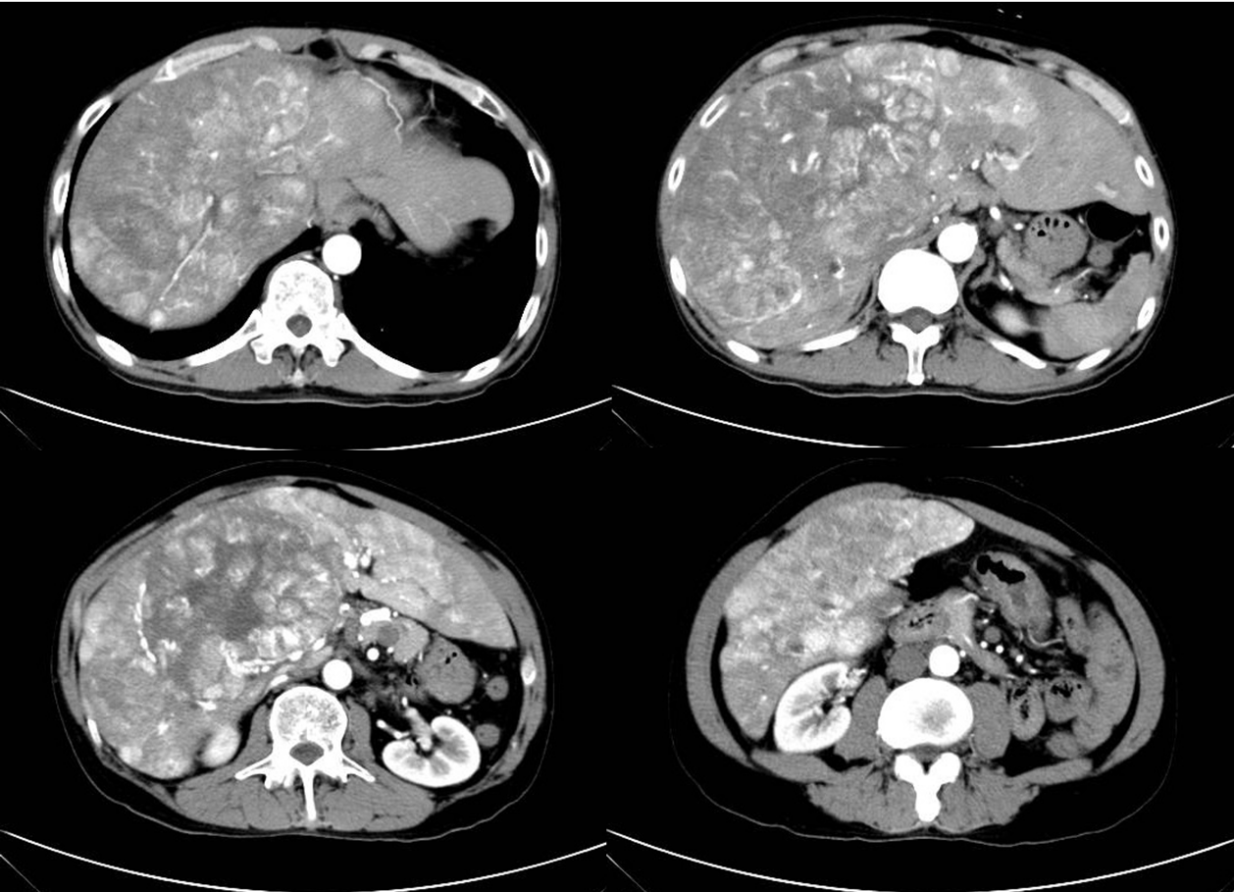

2019年4月下旬,54歲的市民李先生(化名)在單位體檢時發現肝臟多發腫塊,隨即來到柳州市人民醫院肝膽胰外科進一步就診。經完善相關檢查后,李先生被確診為原發性肝癌晚期(巨大肝癌伴多發子灶融合,門靜脈左右支癌栓,正常肝臟僅10%)。這一消息對于李先生家庭來說猶如晴天霹靂,因為像李先生這樣的晚期肝癌患者已經無法進行手術治療,甚至也不適合介入等其他傳統治療,一般預期生存時間僅數個月。

2019年4月26日CT:巨塊型肝癌伴多發子灶融合,門靜脈左右支癌栓形成,正常肝組織僅約10%左右,其余肝臟均被腫瘤侵噬